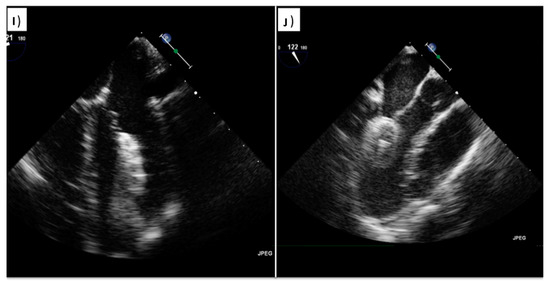

4. ASD

4.2. Perioperative Monitoring

| Before vascular access | Free LA appendage Normal aortic and mitral valve No intracardiac mass Atrial septal aneurysm Eustachian valve Chiari Network Accessory fenestration Antero-posterior septal distance | Free LA appendage No significant mitral valve disease Atrial septal aneurysm Eustachian valve Chiari Network Assess border features Multifenestrated ASD Confirm normal pulmonary vein anatomy Bidimensional and color-based shortest and largest ASD diameter 3D-based shortest and largest ASD diameter |

| After vascular access | Confirm right-to-left shunt at intracardiac bubble study Confirm correct tunnel wiring Confirm wire position in the proper pulmonary vein PFO tunnel amplitude and length | Confirm wire position in the proper pulmonary vein Balloon sizing in stop-flow condition |